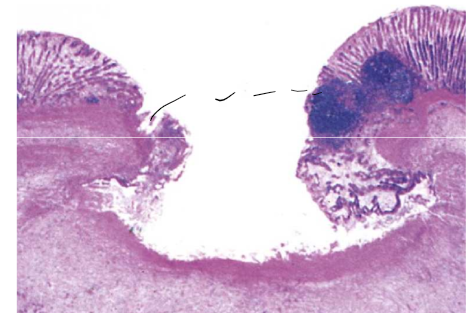

13

Q

quel patron morphologique de l’Inflammation aiguee?

proto(coupe histo) = quoi?

A

ulcère

car cratère a été crée du a une perte de tissu nécrotique

ulcère duodénale